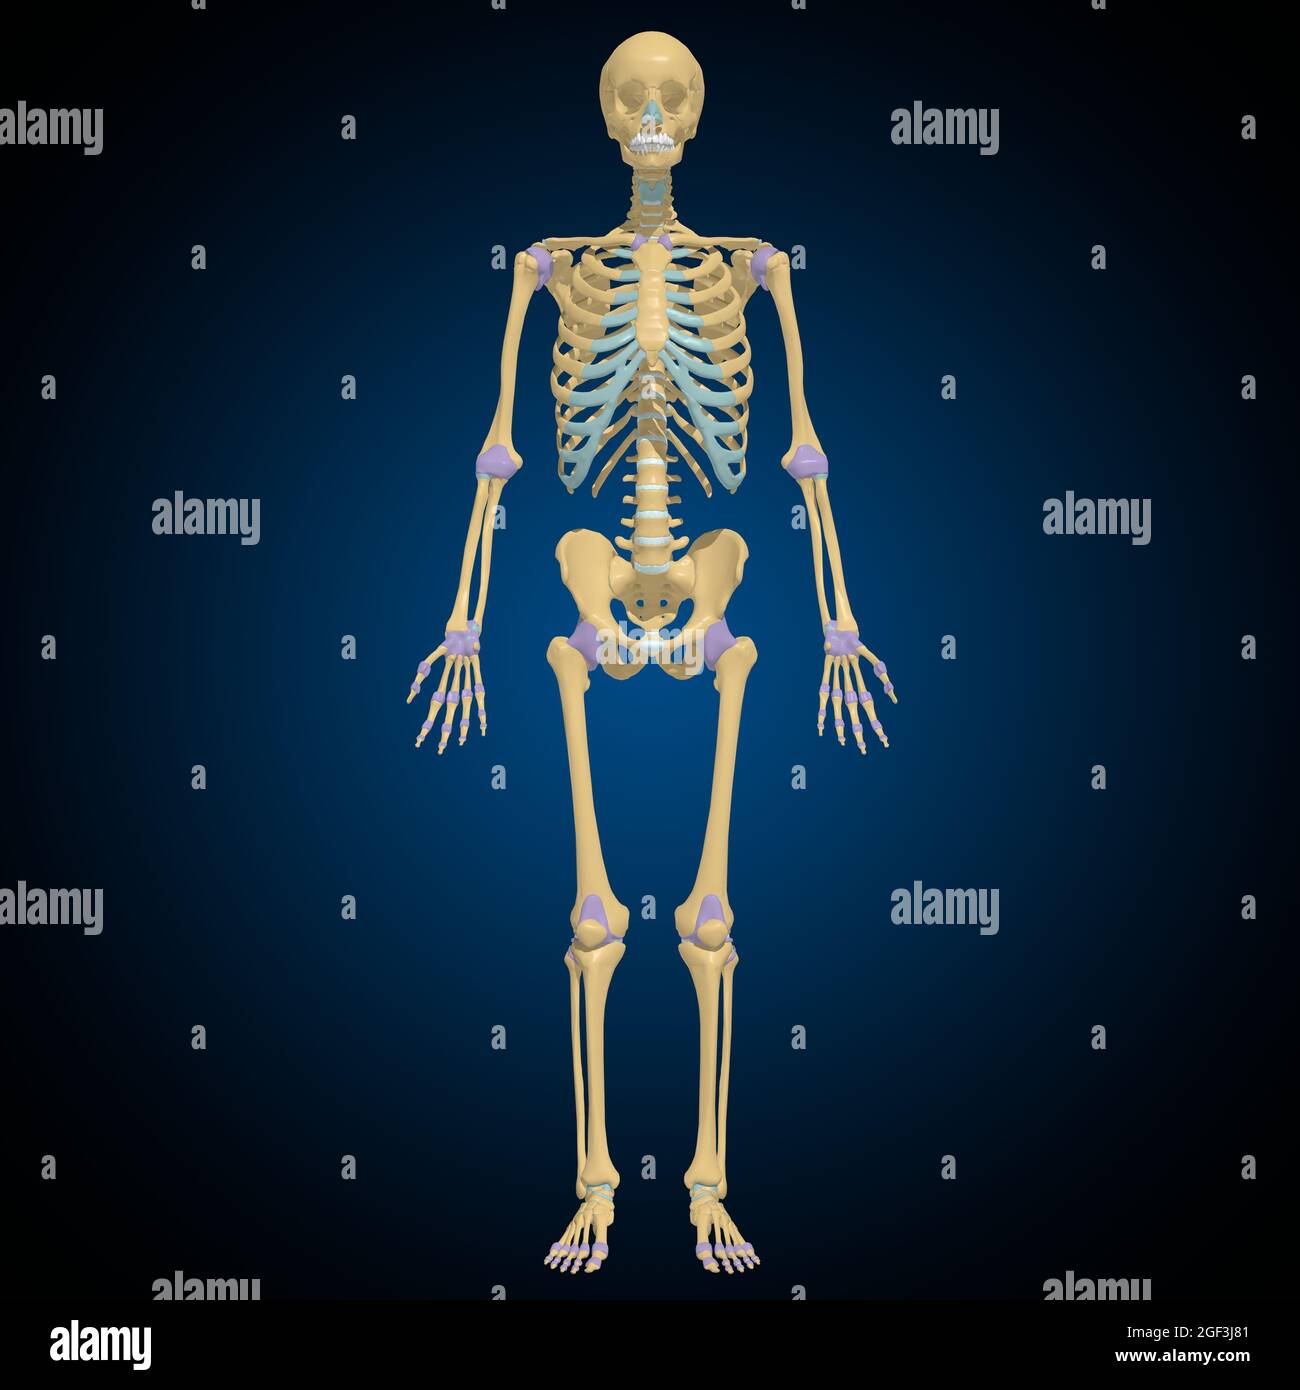

Articular capsule Anatomy For Medical Concept 3D Illustration Stock Photohttps://www.alamy.com/image-license-details/?v=1https://www.alamy.com/articular-capsule-anatomy-for-medical-concept-3d-illustration-image439559253.html

Articular capsule Anatomy For Medical Concept 3D Illustration Stock Photohttps://www.alamy.com/image-license-details/?v=1https://www.alamy.com/articular-capsule-anatomy-for-medical-concept-3d-illustration-image439559253.htmlRF2GF3J8N–Articular capsule Anatomy For Medical Concept 3D Illustration

Articular capsule Anatomy For Medical Concept 3D Illustration Stock Photohttps://www.alamy.com/image-license-details/?v=1https://www.alamy.com/articular-capsule-anatomy-for-medical-concept-3d-illustration-image439559233.html

Articular capsule Anatomy For Medical Concept 3D Illustration Stock Photohttps://www.alamy.com/image-license-details/?v=1https://www.alamy.com/articular-capsule-anatomy-for-medical-concept-3d-illustration-image439559233.htmlRF2GF3J81–Articular capsule Anatomy For Medical Concept 3D Illustration

Articular capsule Anatomy For Medical Concept 3D Illustration Stock Photohttps://www.alamy.com/image-license-details/?v=1https://www.alamy.com/articular-capsule-anatomy-for-medical-concept-3d-illustration-image439559176.html

Articular capsule Anatomy For Medical Concept 3D Illustration Stock Photohttps://www.alamy.com/image-license-details/?v=1https://www.alamy.com/articular-capsule-anatomy-for-medical-concept-3d-illustration-image439559176.htmlRF2GF3J60–Articular capsule Anatomy For Medical Concept 3D Illustration

Articular capsule Anatomy For Medical Concept 3D Illustration Stock Photohttps://www.alamy.com/image-license-details/?v=1https://www.alamy.com/articular-capsule-anatomy-for-medical-concept-3d-illustration-image439559162.html

Articular capsule Anatomy For Medical Concept 3D Illustration Stock Photohttps://www.alamy.com/image-license-details/?v=1https://www.alamy.com/articular-capsule-anatomy-for-medical-concept-3d-illustration-image439559162.htmlRF2GF3J5E–Articular capsule Anatomy For Medical Concept 3D Illustration

Articular capsule Anatomy For Medical Concept 3D Illustration Stock Photohttps://www.alamy.com/image-license-details/?v=1https://www.alamy.com/articular-capsule-anatomy-for-medical-concept-3d-illustration-image439559178.html

Articular capsule Anatomy For Medical Concept 3D Illustration Stock Photohttps://www.alamy.com/image-license-details/?v=1https://www.alamy.com/articular-capsule-anatomy-for-medical-concept-3d-illustration-image439559178.htmlRF2GF3J62–Articular capsule Anatomy For Medical Concept 3D Illustration

Articular capsule Anatomy For Medical Concept 3D Illustration Stock Photohttps://www.alamy.com/image-license-details/?v=1https://www.alamy.com/articular-capsule-anatomy-for-medical-concept-3d-illustration-image439559254.html

Articular capsule Anatomy For Medical Concept 3D Illustration Stock Photohttps://www.alamy.com/image-license-details/?v=1https://www.alamy.com/articular-capsule-anatomy-for-medical-concept-3d-illustration-image439559254.htmlRF2GF3J8P–Articular capsule Anatomy For Medical Concept 3D Illustration